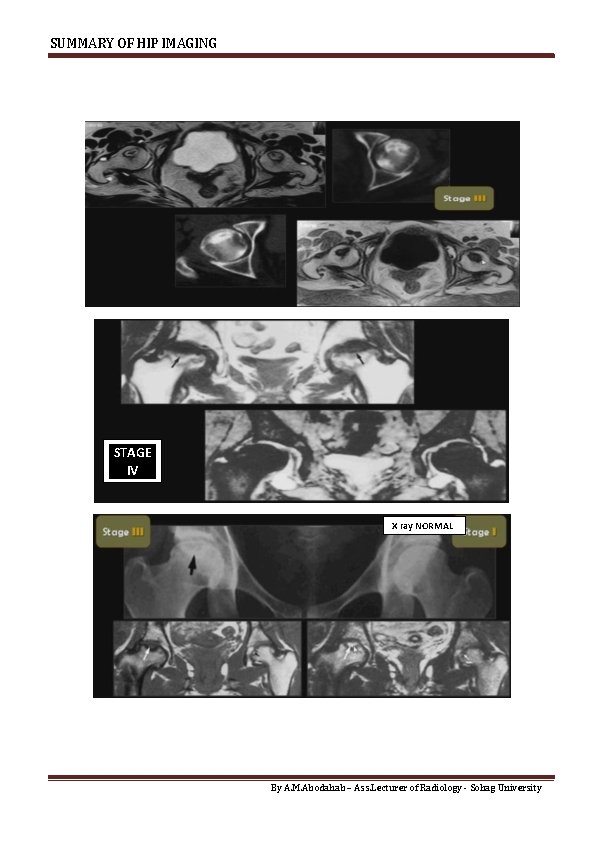

SUMMARY OF HIP IMAGING MRI FINDING II NB. Stage I is not written in

SUMMARY OF HIP IMAGING MRI FINDING II NB. Stage I is not written in Report , but described as "Bone Marrow edema" When Advanced AVN is diagnosed By X-ray No need of MRI Prognosis is related to : o size of lesion < 25 % of head = Good prognosis o Site : Medial Or central better AVN Vs Osteoarthritis In AVN…… Acetabulum & Superior Joint space are not affected. By A. M. Abodahab – Ass. Lecturer of Radiology - Sohag University

SUMMARY OF HIP IMAGING STAGE IV X ray NORMAL By A. M. Abodahab –

SUMMARY OF HIP IMAGING STAGE IV X ray NORMAL By A. M. Abodahab – Ass. Lecturer of Radiology - Sohag University